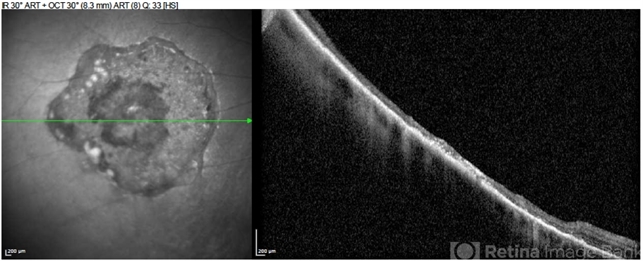

- CHRPE

- Meghan Menzel, University of Iowa

- Imaging device

- Optical coherence tomography system

- Optical coherence tomography image over a CHRPE lesion.